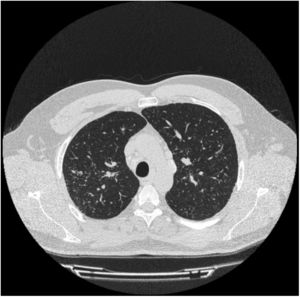

Varón de 36 años, trabajador de tallado de roca ornamental desde 20 años antes (exposición laboral continua a cuarzo, granito, mármol…) y fumador activo de 5 paquetes-año. Consultó por episodios de artritis en codos, muñecas e interfalángicas proximales, con rigidez matutina y limitación para la flexión de la mano, que mejoraba a lo largo del día, de un año de evolución. Se acompañaba de disnea de moderados esfuerzos y de sequedad oral y ocular de un año de evolución. A la exploración física destacaba inflamación y edema articular de interfalángicas proximales, muñeca y codo izquierdo. La auscultación pulmonar fue normal. La analítica mostró elevación de reactantes de fase aguda (VSG 35mm y PCR 25mg/l) y anticuerpos anti-Ro y anti-La fuertemente positivos. El resto de los parámetros (ANA, factor reumatoide y anticuerpo anticitrulinado) fueron negativos. El test de Schirmer fue patológico (3mm) y la gammagrafía de glándulas salivares puso de manifiesto una hipofunción moderada-severa de las glándulas parótidas y submaxilares. La TC de tórax (fig. 1) reveló la presencia de adenopatías mediastínicas e hiliares así como un patrón micronodulillar difuso en campos superiores. Las pruebas de función respiratoria (espirometría, pletismografía, disfusión y test de la marcha) fueron normales. Con el diagnóstico de silicosis y SS, debido a la intensidad de sus artritis, se inició tratamiento con prednisona en dosis descendente e hidroxicloroquina, con mejoría posterior del paciente.

–definidas como presencia de sintomatología o de alteración funcional– en el SS oscila entre el 9 y el 22% de los pacientes y, si se considera la enfermedad subclínica, cercana al 50%11. El espectro de las manifestaciones pulmonares del SS primario abarca tres grupos: anormalidades de la vía aérea (bronquiolitis, hiperreactividad bronquial y bronquiectasias), enfermedad pulmonar intersticial (neumonía intersticial no específica, neumonía intersticial usual, neumonitis intersticial linfocítica y neumonitis organizada) y otro grupo misceláneo (linfoma pulmonar, amiloidosis, hipertensión pulmonar y tromboembolismo pulmonar)12. El caso expuesto presenta la manifestación clásica de la silicosis simple: patrón nodular difuso y bilateral de predominio en ambos lóbulos superiores.